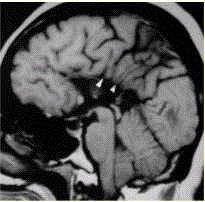

问题 患者女,43岁。智力低下。MRI结果如下图所示。 可能的诊断是

选项 A.胼胝体缺如 B.脑裂畸形 C.灰质异位 D.结节性硬化 E.Sturge-weber综合征

答案 A